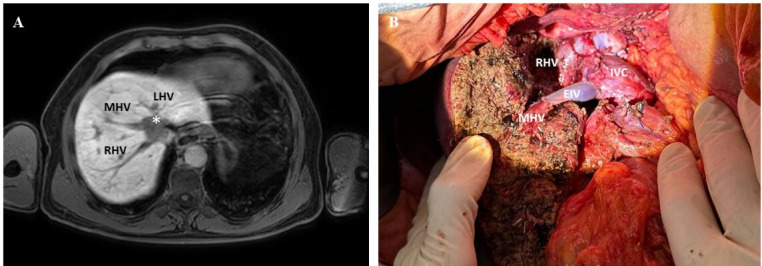

Results: Segmental resection was performed in four cases, two with graft interposition. Patch reconstruction was performed for three HVs and two inferior vena cava resections. Two cases required primary closure. No mortality was observed, while the major morbidity rate was 33%. The short-term and long-term patency of the reconstructed HVs was 88.9% and 66.7%, respectively. HV reconstructions allowed the preservation of additional parenchyma (mean 495.4 mL, 95% CI 350.2 to 640.7). A decision-making algorithm to be used within the described approach is proposed.